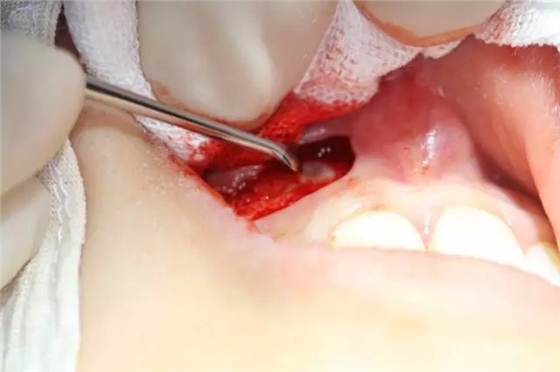

病例資料: 患者、柴xx、女、16歲。??茩z查及病歷如下圖: 患者同意我院正畸科建議,遂轉(zhuǎn)診倒外科。術(shù)前簽知情同意書。 治療過(guò)程: 圖1.術(shù)前的CBCT檢查:13阻生,疑為含牙囊腫??v剖面顯示12牙根吸收至根尖1/3。 圖2.局部麻醉下 。行唇側(cè)弧形切口,12松動(dòng)不到1°。 圖3.翻瓣、暴露骨面。 圖4.去骨、 暴露13牙冠 圖5.去骨、逐漸顯露13。 圖7.拔除13. 圖8.摘除囊壁 圖9.必須完整剝離囊壁。 圖10.摘除囊壁后形成的骨腔 圖11.超聲骨刀12根尖倒預(yù)備 圖13. 消毒棉球骨腔內(nèi)隔濕血液,紙尖干燥倒預(yù)備好的根管 圖14. 紙尖無(wú)血即可 圖15。MTA倒充填 圖16.骨腔填塞膠原蛋白海綿 圖17.拔除的13及摘除的囊壁 圖18.縫合 圖19.術(shù)后x線根尖片影像:MTA封閉根尖